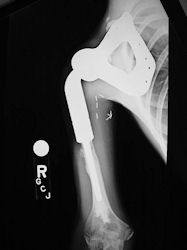

Examples of radical limb sparing surgeries for osteosarcomas in various anatomic locations (distal femur, proximal tibia, proximal humerus, scapula)

In each case, the tumor and bone from which it arose were resected. This required meticulous dissection, mobilization and preservation of adjacent pertinent neurovascular structures. In each case presented here, the defect was reconstructed with a special modular segmental tumor prosthesis. This also replaces the adjacent joint in many instances.

Proximal Humerus: Radical Limb Sparing Extra-Articular Resection and Prosethetic Reconstruction